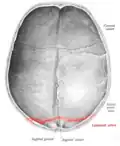

![]() Lambdoid suture (labeled at bottom right) | |

The lambdoid suture, or lambdoidal suture, is a dense, fibrous connective tissue joint on the posterior aspect of the skull that connects the parietal bones with the occipital bone. It is continuous with the occipitomastoid suture.

The lambdoid suture is between the paired parietal bones and the occipital bone of the skull. It runs from the asterion on each side.

The lambdoid suture is named due to its uppercase lambda-like shape.